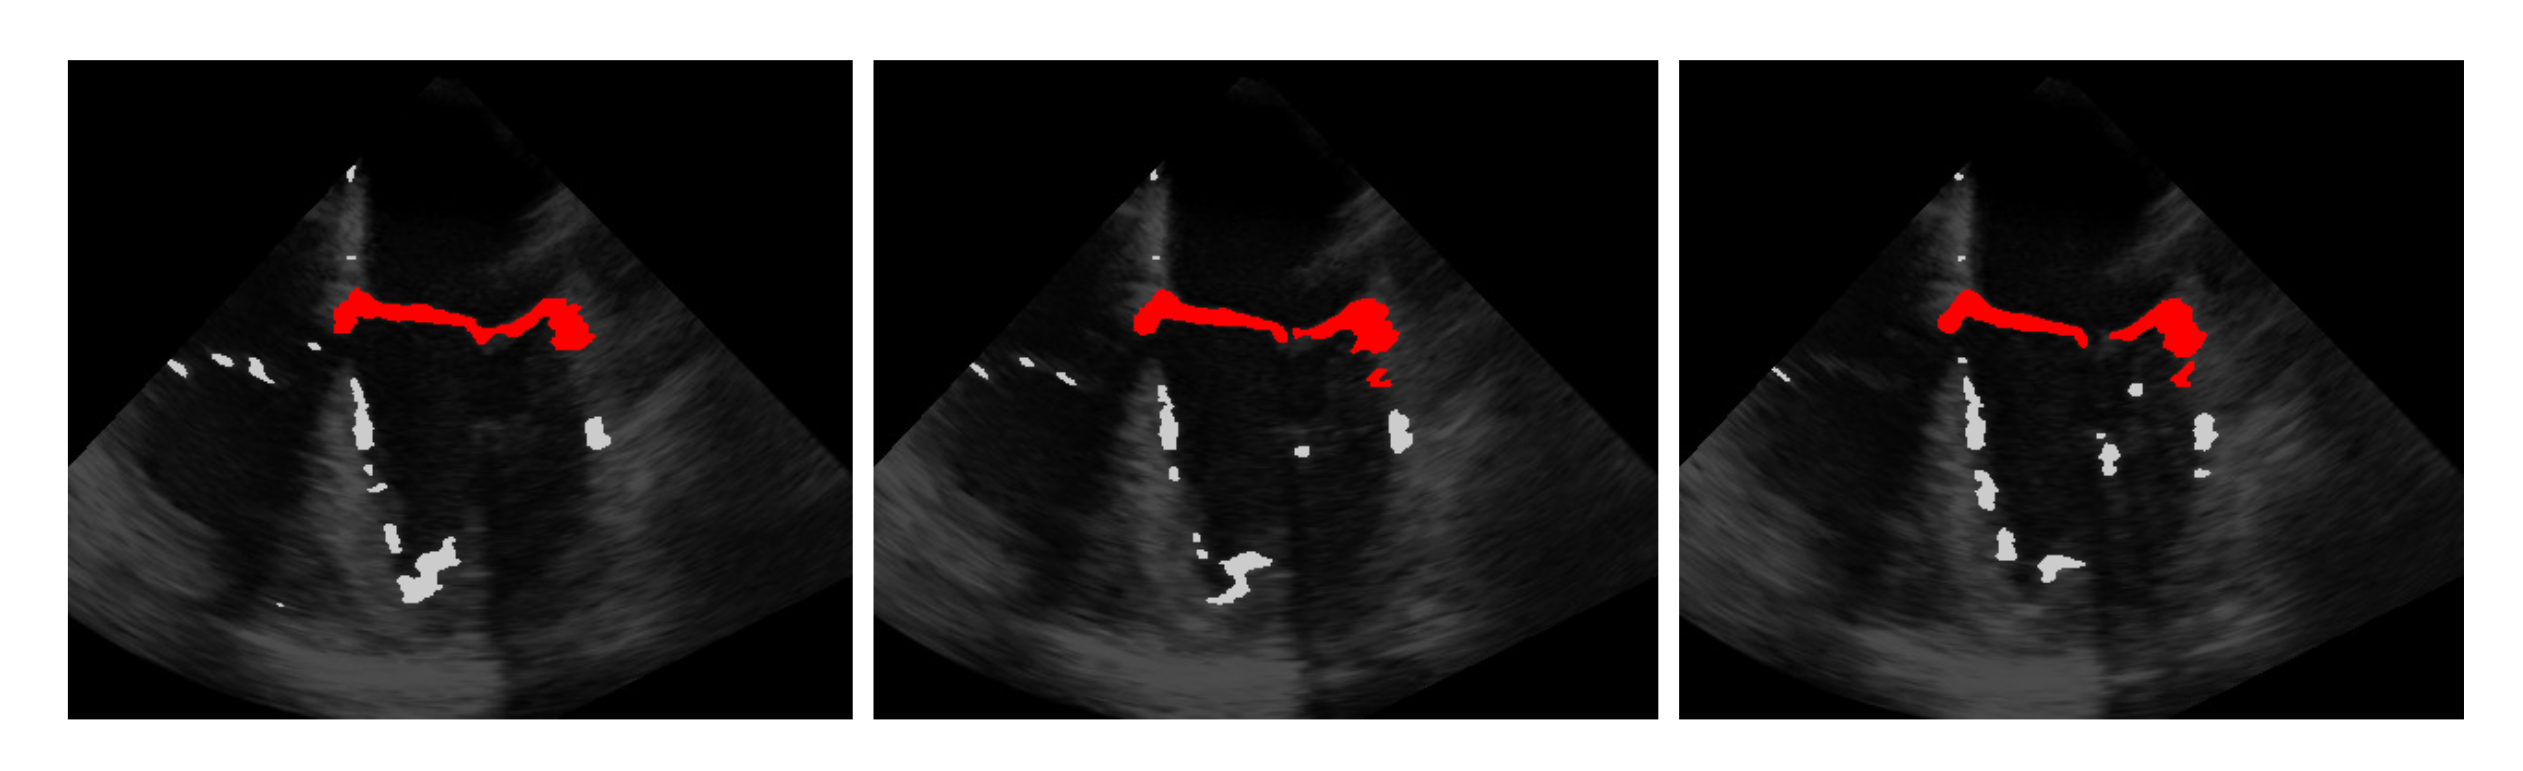

5.1. On Bregman Iteration and RNMF

5.2. Automatic Segmentation